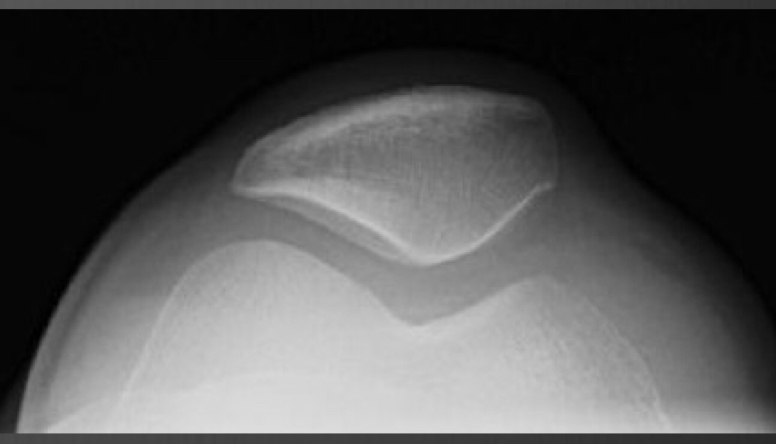

sunrise view of the patella

● Perpendicular - axial plane (sunrise and axial)